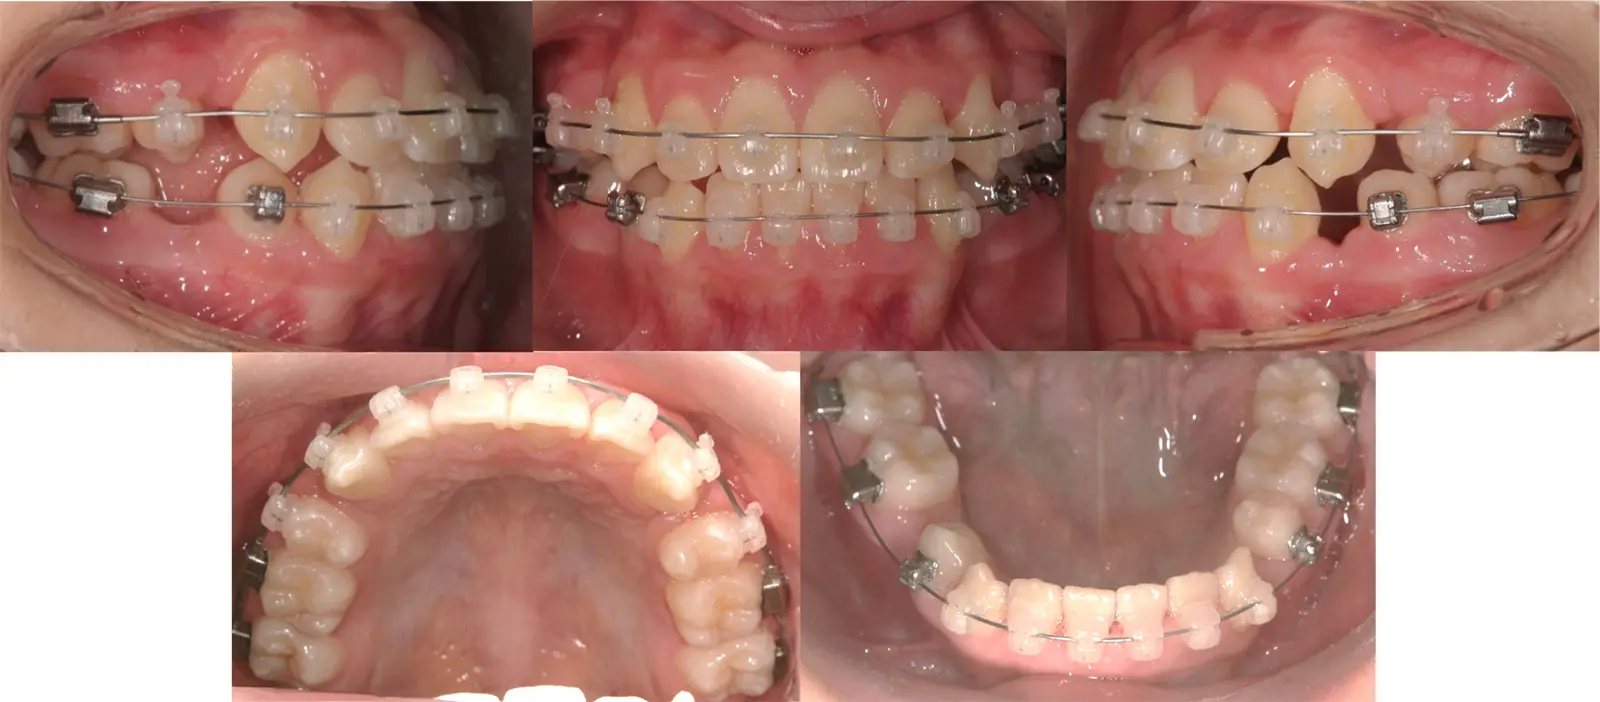

アングルⅠ級、過蓋咬合を伴う叢生

乱食い歯

- 年齢

20代

- 治療期間

1年7ヶ月

- 治療回数

18回

- 治療に用いた主な装置

上下顎共にカスタムメイド型リンガルブラケット矯正装置 (WIN)

- 治療費

1,350,000円(税別)トータル料金

- 抜歯部位

非抜歯治療による治療